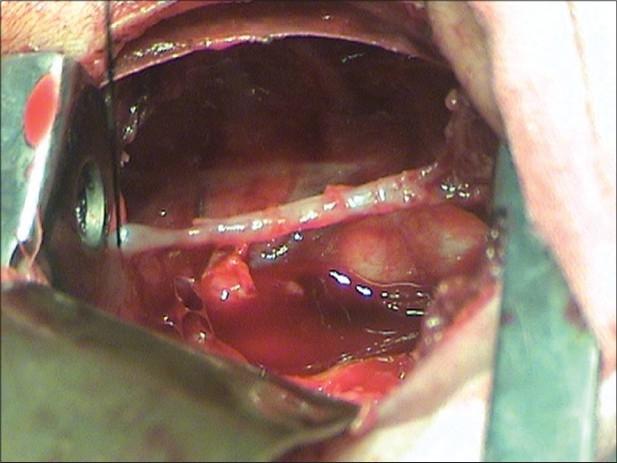

Several theories on embryogenesis of esophageal atresia have been proposed, none could explain the whole spectrum of this anomaly. We report a new variant of esophageal atresia in which the two blind pouches were joined by an atretic band. Histology of the atretic part showed groups of striated muscle arranged haphazardly without any lumen. The existing theories on etiology of esophageal atresia cannot explain this variant. However, localized vascular accident during intrauterine life resulting in disturbances in regional microcirculation could be a possible factor as demonstrated by Louw and Barnard in relation to jejunoileal atresia. This is contrary to the current understanding that disproportionate growth of the horizontal esophageal folds results in esophageal atresia.

关于食管闭锁的胚胎发生已经提出了几种理论,但没有一种能够解释这种异常的全貌。我们报告了一种食管闭锁的新变体,其中两个盲袋由一条闭锁带相连。闭锁部分的组织学显示横纹肌束杂乱排列,没有任何管腔。现有的食管闭锁病因理论无法解释这种变体。然而,宫内生活期间局部血管意外导致局部微循环障碍可能是一个因素,正如Louw和Barnard在空肠闭锁方面所证明的那样。这与目前认为水平食管皱襞生长不均衡导致食管闭锁的观点相反。